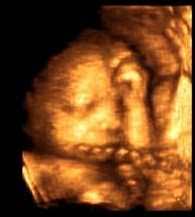

35.HAFTA ANNE KARNINDA BEBEK GELİŞİMİ

Bebekteki değişiklikler

Bebek yaklaşık 2.5 kilo ağırlığındadır. Poposundan başına uzunluğu 33 cm. olup toplam uzunluğu da 45 cm.'dir.Bebeğiniz yağ depolamaya devam eder ve özellikle omzunun etrafında boğumlar ve tombulluklar oluşmaya başlar. Siz yaklaşık haftada 350-500 gr alırken , bebek artık , kabaca sizin her hafta aldığınız kilonun yarısı kadar kilo almaktadır( 180-250 gr ). Artık içinde yüzdüğü suya oranla rahim içinde daha fazla yer kaplamaya başladığından hareketleri de çok kolay olmayacaktır.Bebeğinizin göz rengi mavidir, ancak sonrasında değişecektir.Bebeğiniz artık bu haftadan sonra doğuma hazırdır.